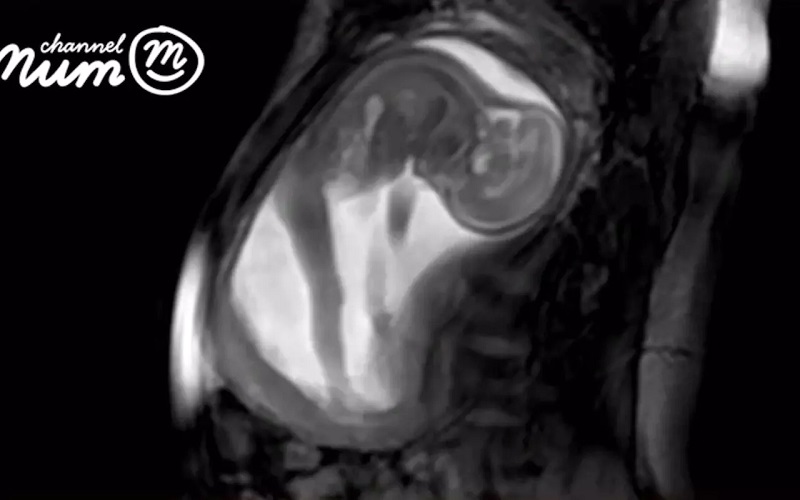

Погледнете го најдеталниот ултразвук на светот

Интернационален тим на истражувачи направиле најјасни слики на фетус до сега.

Деталните слики биле направени со помош на компјутерска технологија и ултразвук. Во видеото може да се види како плодот игра со папочната врвца, ја врти главата и се протегнува во мајчината утроба. Видеото завршува со клоцање со двете нозе, предизвикувајќи поместување на стомакот на мајката.

Оваа технологија е развиена од истражувачи од „iFind“, проект финансиран со 10 милиони фунти од  „Wellcome Trust and the Engineering and Physical Sciences Research Council (EPSRC)“. Нивната цел е на ваков начин да се детектираат абнормалностите на фетусот на време, па плодот може да се третира уште пред да биде роден.